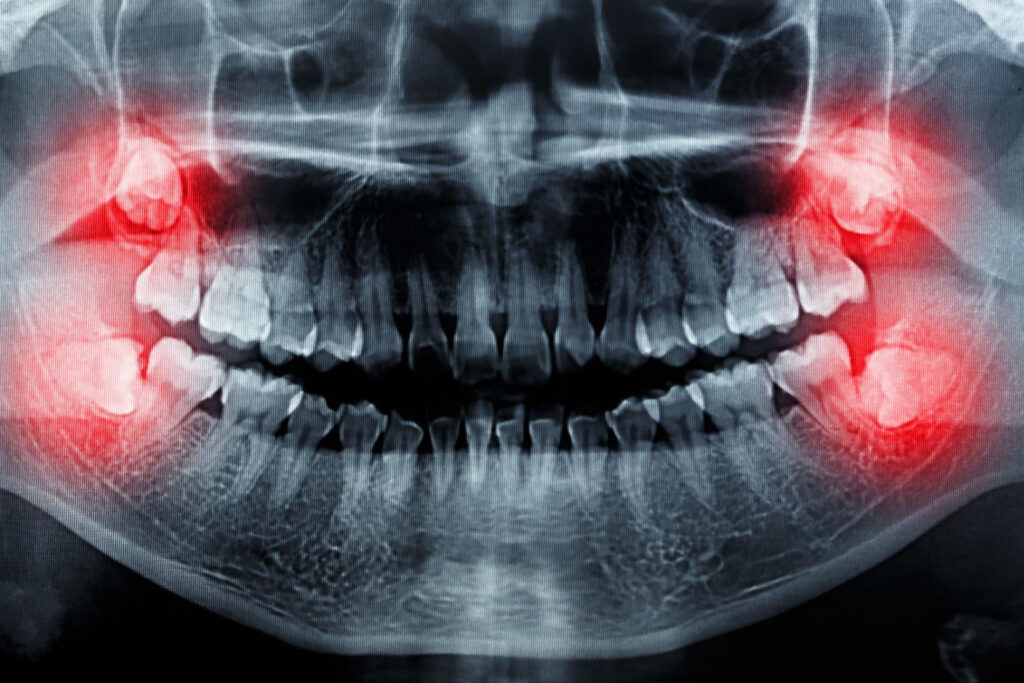

The eighth tooth is the last in the series, this is the wisdom tooth. He got this name because he breaks through the gums between the ages of 18 and 25, when one has the most common knowledge according to common belief. The bottom eighth tooth is generally the largest tooth in the oral cavity.

The badly lying wisdom teeth cause various problems that you perceive of course. If you have no symptoms, it is best to ask your dentist about their condition. Regular x-rays can follow their condition, and so they can be coordinated with the other teeth.

The problems come from the fact that our jaw has become anatomically smaller with the progress of evolution, as a result of which these teeth no longer have any space. For most young people – about three of four – there is not enough anatomical space for wisdom teeth in the row so sooner or later the majority of the adult population will encounter difficulties.

In the lucky case, the wisdom teeth begin to grow and break. The worst situation occurs when they can not break through the gums. There are countless possibilities between these two extremes.

Tooth removal is recommended when the wisdom tooth is positioned so that there is no chance for it to break through and causes recurrent inflammation and pain. If other ailments occur, such as tooth decay, or because of difficult cleaning gingivitis, it is also worth pulling them out.

It is also rare that an X-ray suspects a sometimes malignant change, in which case it is of course important to remove it as soon as possible.